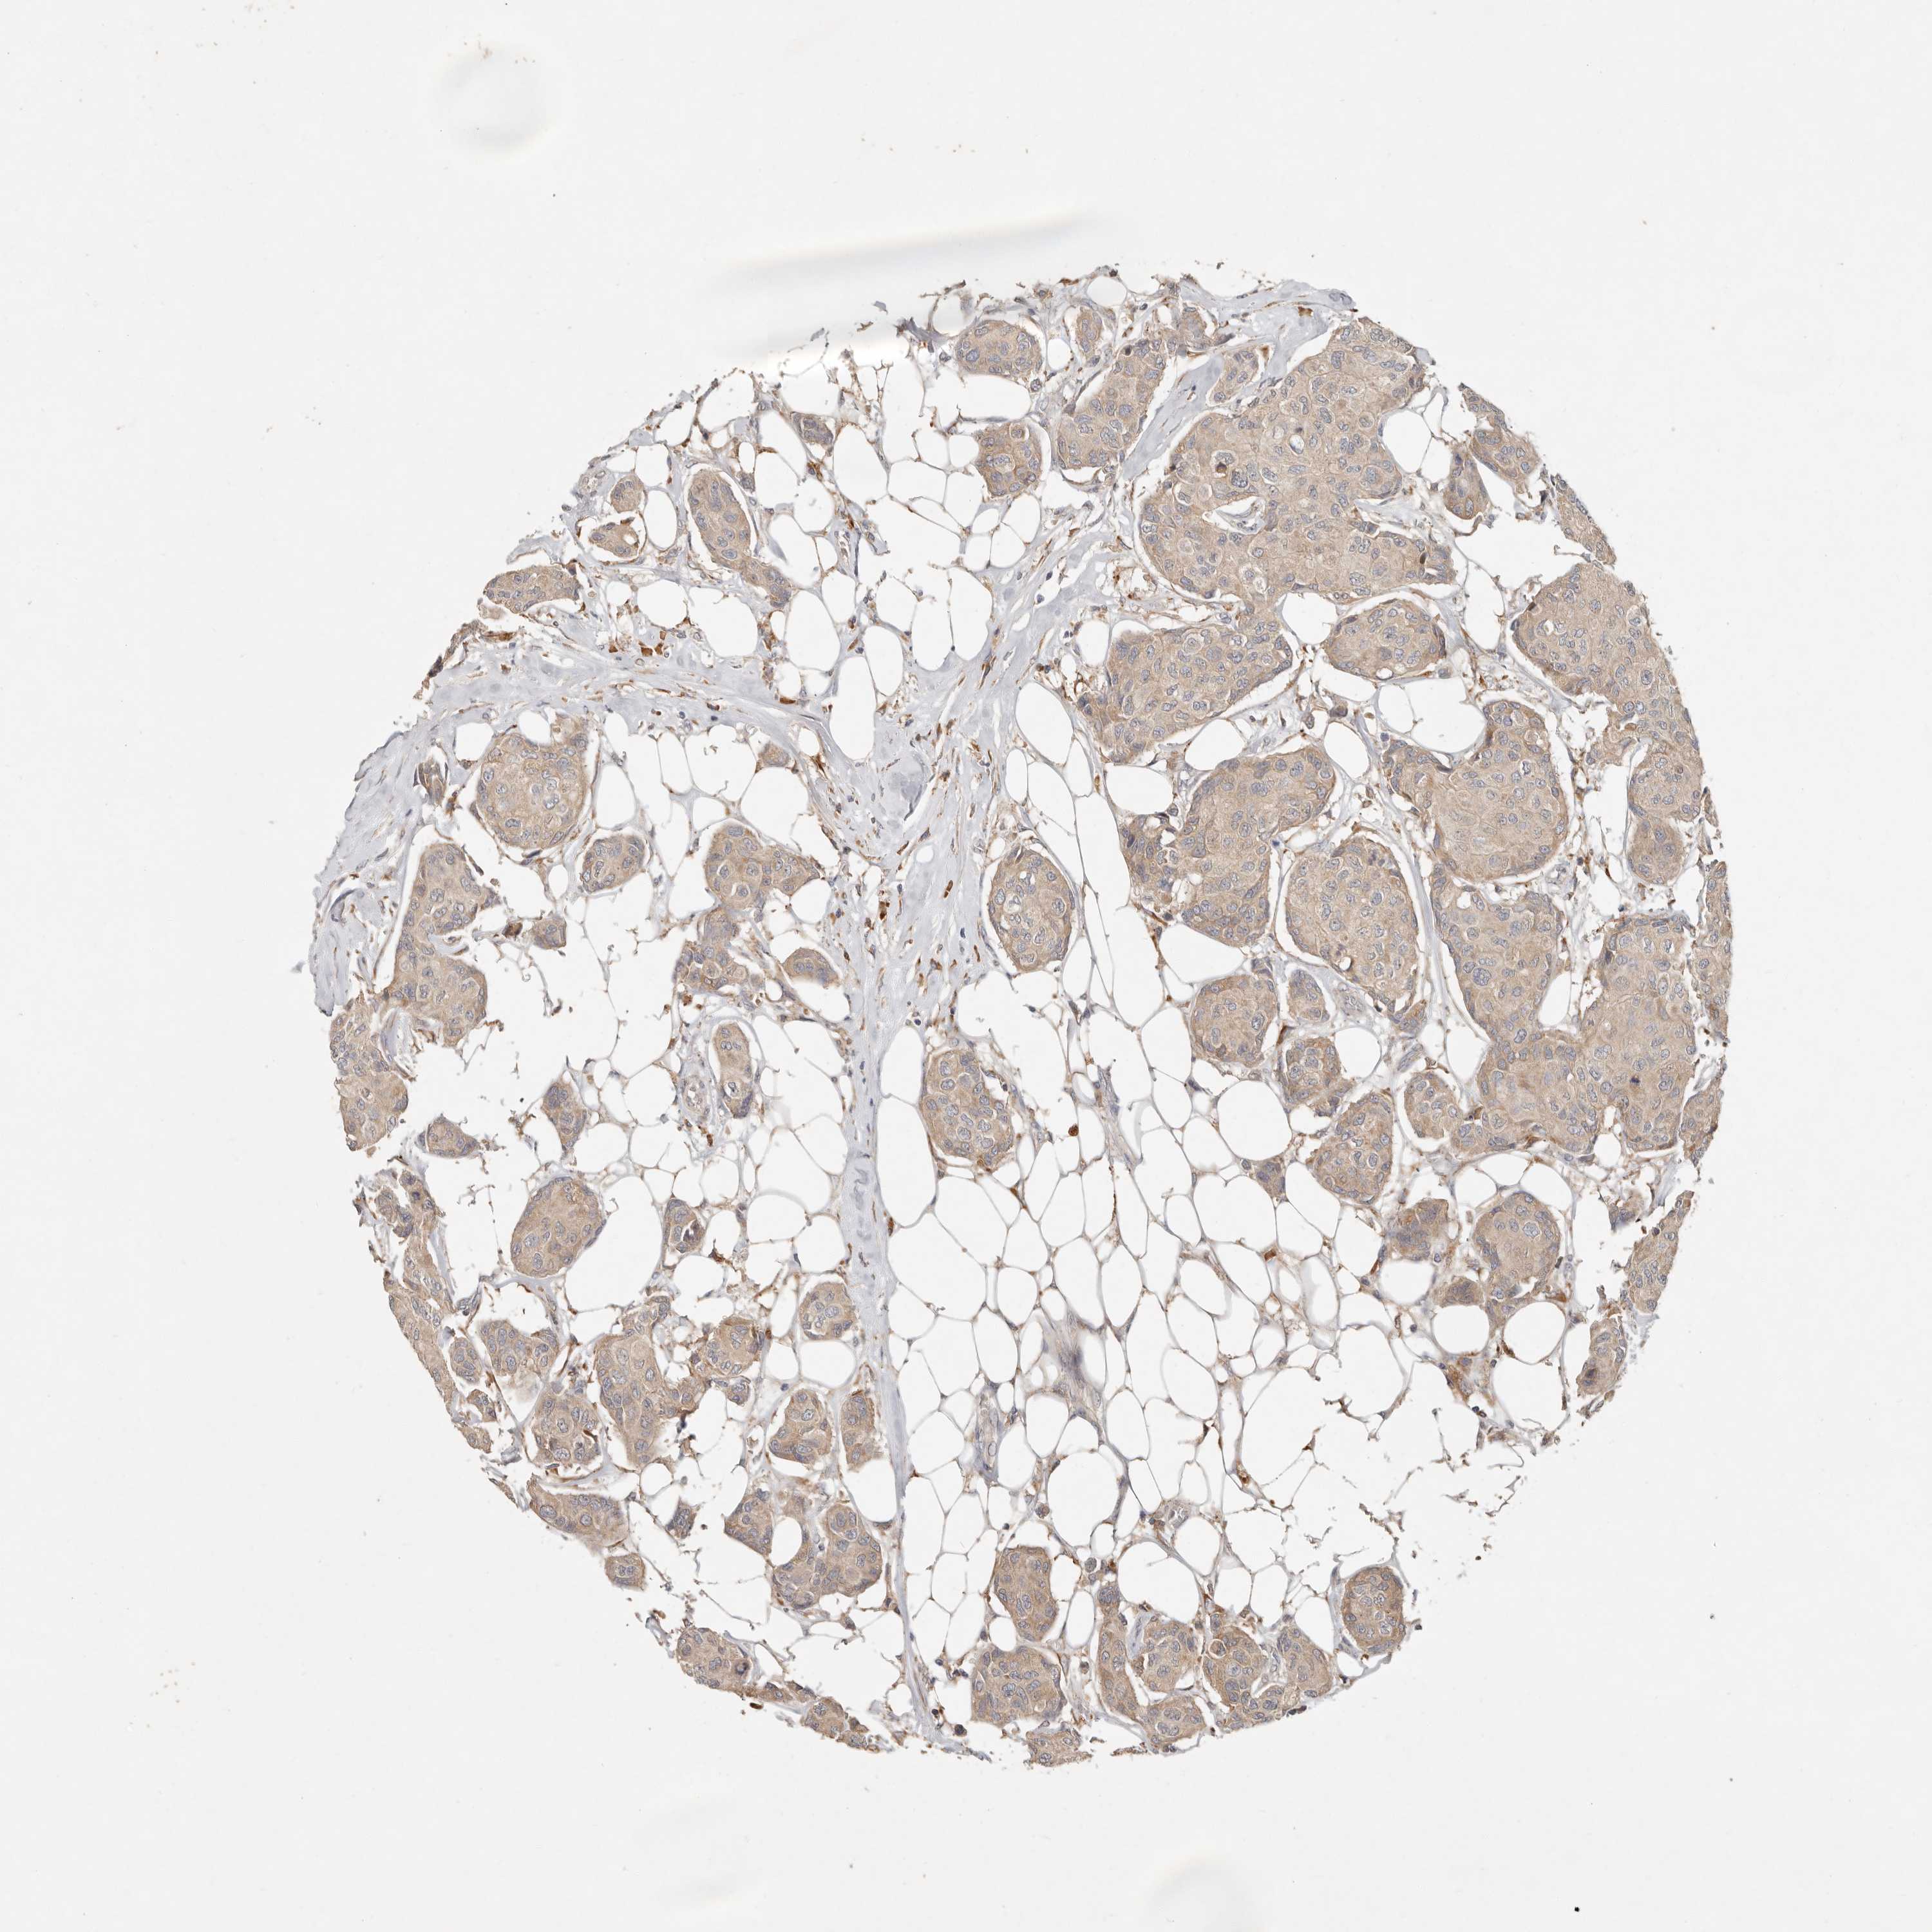

BRCA TCGA BRCA VALIDATION PROTEIN EXPRESSION